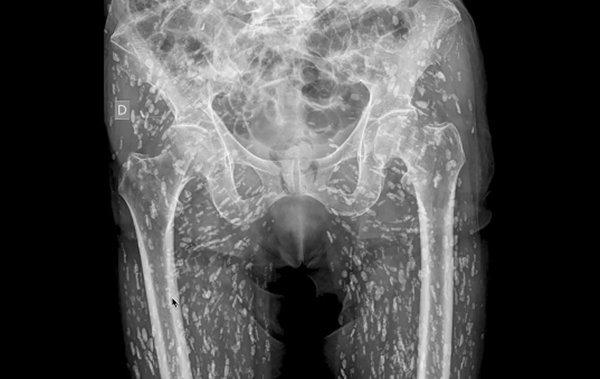

หมอเผยภาพเอกซเรย์ชวนสยดสยอง สีขาว ๆ ที่เห็นคือความสะพรึง มีมาถึงต้นขา เกิดจากอะไร เตือนสิ่งที่ไม่ควรทำ

วันที่ 21 มกราคม 2568 เว็บไซต์อ็อดดิตี้เซ็นทรัล เผยว่า เมื่อเร็ว ๆ นี้ มีแพทย์ห้องฉุกเฉินรายหนึ่ง ได้เผยภาพเอกซเรย์ที่น่าตกตะลึง โดยเขาระบุว่าเป็น "ภาพเอกซเรย์ที่บ้าที่สุดเท่าที่เขาเคยเห็นมา" เมื่อแสดงให้เห็นว่าภายในร่างกายส่วนล่างของผู้ป่วยเต็มไปด้วยจุดสีขาวเล็ก ๆ มากมายเกินกว่าร้อยจุด กระจายอยู่ทั่วบริเวณตัวมาจนถึงที่ต้นขา โดยจุดสีขาวที่เห็นในภาพเอกซเรย์นี้ก็คือ ไข่ของพยาธิตัวตืดที่กลายเป็นหินปูน

ดร.แซม กาลี แพทย์ประจำแผนก ER ผู้เชี่ยวชาญด้านภาวะฉุกเฉินทางหัวใจและหลอดเลือดและรังสีวิทยาฉุกเฉิน ในสหรัฐอเมริกา ได้แชร์ภาพเอกซเรย์บริเวณอุ้งเชิงกรานของผู้ป่วยรายหนึ่ง ซึ่งได้เข้ามาขอรับการรักษา ภาพหลังจากประสบอุบัติเหตุล้มและมีอาการปวดสะโพก โดยที่เขาไม่เคยล่วงรู้มาก่อนเลยว่า มีไข่พยาธิตัวตืดที่กลายเป็นหินปูน ซ่อนอยู่ในตัวของเขาเป็นจำนวนมากมายเช่นนี้ และเขาก็ไม่เคยรู้เรื่องเกี่ยวกับพยาธิตัวตืดมาก่อนด้วยเช่นกัน

พยาธิตัวตืดเป็นปรสิตที่มักจะเกาะติดอยู่ภายในลำไส้เพื่อดูดซับสารอาหาร แต่ไข่พยาธิตัวตืดยังสามารถเดินทางไปได้ทุกที่ภายในร่างกาย ตั้งแต่เท้าไปจนถึงสมอง เมื่อเวลาผ่านไป ไข่พยาธิตัวตืดเหล่านี้จะกลายเป็นหินปูน และไม่สามารถดำรงชีวิตได้อีกต่อไป หากไข่พยาธิตัวตืดเข้าไปเกาะในเนื้อเยื่ออ่อน เช่น กล้ามเนื้อหรือไขมัน ก็อาจจะไม่เป็นภัยคุกคามถึงชีวิต แต่หากขึ้นไปที่สมอง ก็สามารถทำให้เกิดภาวะที่เป็นอันตรายถึงชีวิตได้

ดร.แซม อธิบายสถานการณ์ในภาพเอกซเรย์ดังกล่าว ระบุว่า "สิ่งนี้เรียกว่า โรคถุงพยาธิตืดหมู (Cysticercosis) เป็นโรคที่เกิดจากตัวอ่อนของพยาธิตืดหมูไปฝังตัวตามอวัยวะต่าง ๆ ของร่างกายคน และสามารถแพร่กระจายไปทั่วร่างกายได้ โดยส่วนใหญ่ไปอยู่ที่กล้ามเนื้อและเนื้อเยื่ออ่อนบริเวณสะโพกและขา"